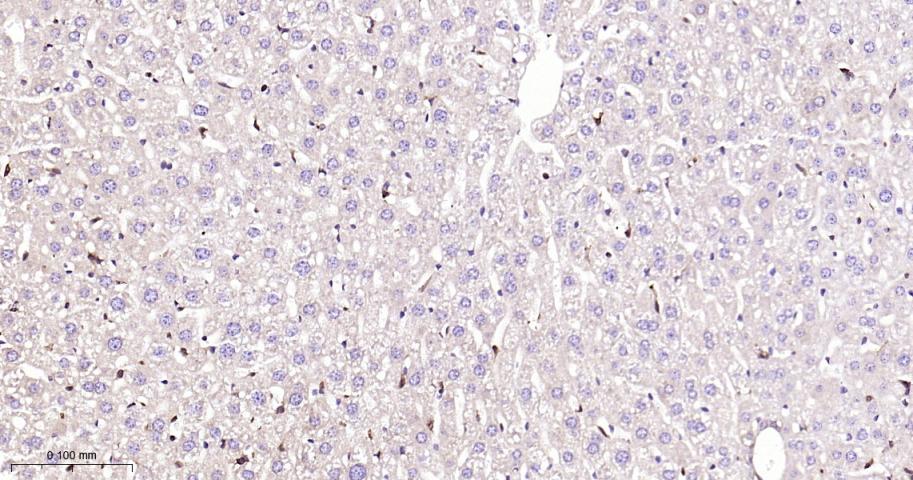

Paraformaldehyde-fixed, paraffin embedded Human Liver; Antigen retrieval by boiling in sodium citrate buffer (pH6.0) for 15 min; Antibody incubation with STAT1 Monoclonal Antibody, Unconjugated(bsm-63166R) at 1:200 overnight at 4°C, followed by conjugation to the bs-0295G-HRP and DAB (C-0010) staining.

Paraformaldehyde-fixed, paraffin embedded Rat Liver; Antigen retrieval by boiling in sodium citrate buffer (pH6.0) for 15 min; Antibody incubation with STAT1 Monoclonal Antibody, Unconjugated(bsm-63166R) at 1:200 overnight at 4°C, followed by conjugation to the bs-0295G-HRP and DAB (C-0010) staining.

Paraformaldehyde-fixed, paraffin embedded Mouse Liver; Antigen retrieval by boiling in sodium citrate buffer (pH6.0) for 15 min; Antibody incubation with STAT1 Monoclonal Antibody, Unconjugated(bsm-63166R) at 1:200 overnight at 4°C, followed by conjugation to the bs-0295G-HRP and DAB (C-0010) staining.